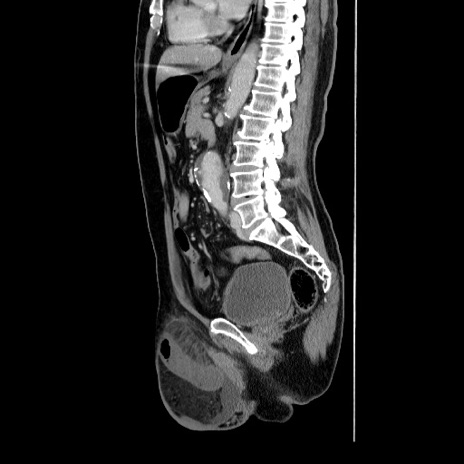

症例34(矢状断像)

【症例】60歳代 男性

【主訴】右鼠径部膨隆

【現病歴】1年程前より右鼠径部膨隆あり。自己にて還納可能だったため放置していた。3時間前より右鼠径部の脱出を認め、還納困難となり受診。

【既往歴】高血圧

【身体所見】右鼠径部に小児頭大の膨隆あり。弾性硬であり、用手還納は困難。左鼠径部にも膨隆を認める。脱出はなし。